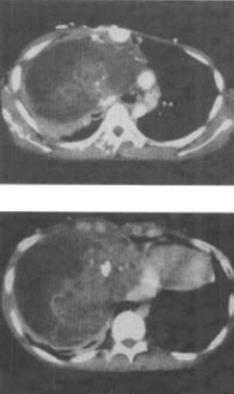

患者男,37岁,咳嗽,咯血2个月余,偶尔咳出钙化物,结合影像学检查,最可能的诊断是()。

A、畸胎瘤

B、肺癌

C、胸腺瘤

D、淋巴管瘤

E、淋巴瘤

A